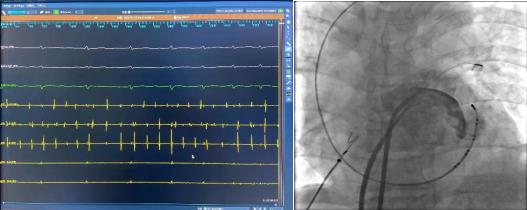

術(shù)前腔內(nèi)電圖可見毫無規(guī)律的房顫波,接著穿刺房間隔建立左房通路。完成肺靜脈隔離及頂部線消融后房顫轉(zhuǎn)復為規(guī)律的心房撲動。

冠狀竇造影定位Marshall靜脈,應用OTW球囊進行酒精消融